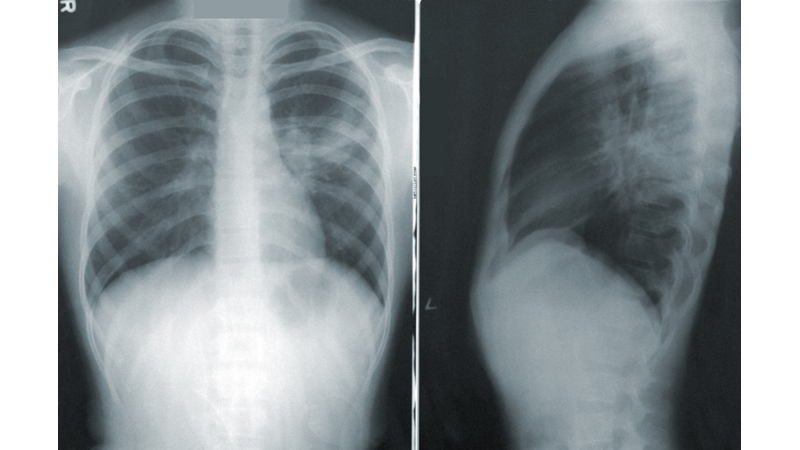

Tıbbi adı 'pnömoni' olan halk arasında zatürre olarak bilinen hastalık; bakteri, virüs, mantar gibi çeşitli mikroorganizmalar nedeniyle oluşan ve akciğer dokusunu etkileyen, en fazla ölüme yol açabilen ve bulaşıcı olan bir enfeksiyon hastalığıdır.

Zatürrede en riski yaş grupları 5 yaş altı çocuklar ve 65 yaş üzeri erişkinlerdir. Kronik hastağı olanlar enfeksiyona daha yatkın olduğu için daha fazla risk altındadırlar. Bunlara rağmen pnömoni, tedavi edilebilir ve önlenebilir bir hastalıktır. Aşılama en önemli koruyucu önlemdir.